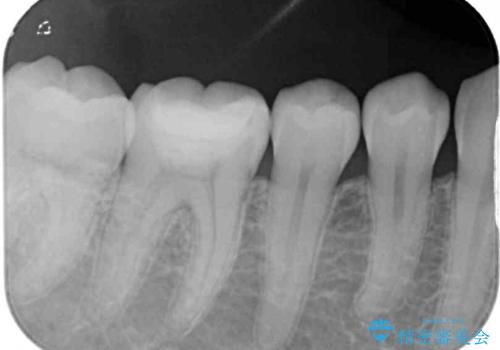

むし歯治療した歯にセラミックを入れたい セラミックインレー修復

- 他院にてむし歯の治療をし、当院にてセラミックを入れたいとのことで来院された患者様です。

むし歯がないか確認し、セラミックインレーにて修復することとしました。

見た目、噛み合わせともに満足していただけました。